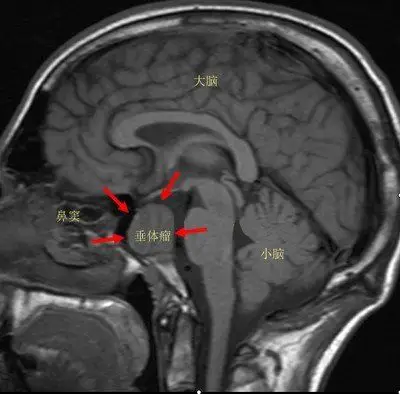

位于颅底垂体窝内,借垂体柄与丘脑下部相连,分腺体部和神经部.

垂体( pituitary gland)位于垂体窝内,借垂体柄,经膈孔与第三脑室底的

图2-3-2垂体 1垂体前叶 2垂体柄 3垂体后叶